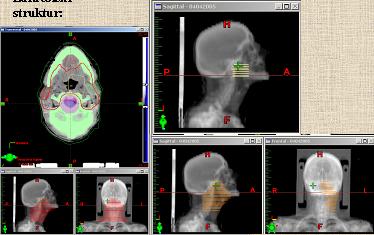

Plánování RT

Srovnání 3D CRT a IMRT

3D CRT

Lokalizace a plánovací CT

Zakreslení struktur – (PTV, rizikové struktury)

Technika, umístění polí, lamely MLC

Váhování polí

Simulace

Verifikace

IMRT

Lokalizace a plánovací CT s kontrastem

Zakreslení struktur – (PTV, rizikové a pomocné struktury)

Počet a umístění polí

Optimalizace, constrains

Simulace – setupová pole

Verifikace – setupová pole